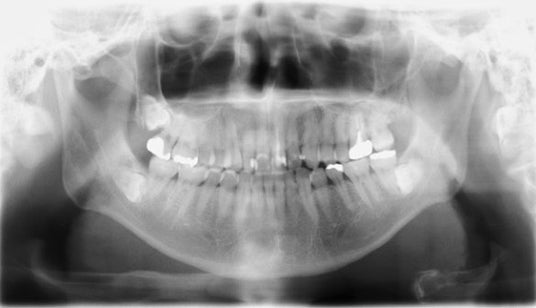

【図3‐1】の画像はCBCT/パノラマ複合機のフラットパネルで撮影されたパノラマ画像です。

全体的に画像にザラツキがありますが、特に真ん中の部分が白くなっています。これは、どうしても歯を全体的に撮影しようとすると頸椎が映りこんでしまう影響です。

見て頂けると分かるように、これでは特に前歯の部分の画像がボケて詳細な診断までは難しく、多くの歯科医が画像に対する不満をお持ちです。